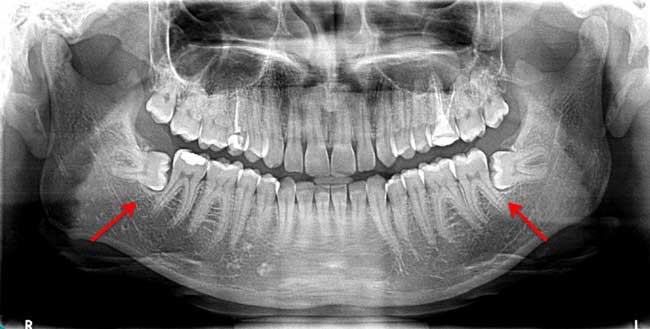

Not all coming wisdom teeth required to remove, if it is not causing any difficulty or pain you should not worried, still visit dental clinic for assessment of your wisdom tooth position by dental x-ray.

Dentist will recommend that they be removed early if they appear to be coming in at an angle or if they are misaligned, to prevent problems down the line.

Dentist may take your x ray of wisdom tooth and he or she will decide the treatment plan for wisdom tooth removal

The time of wisdom tooth surgery may vary from one person to another depending upon difficulty level of surgery. If they are straight and in proper alignment, removal is fairly straightforward, much likes the removal of any other molar.

However, if they are angled, impacted or embedded in the bone, or have been infected or an abscess has formed, they can be little difficult to remove. Usually Wisdom teeth surgery time takes around 30 minutes. It depends on your particular case, but typically it will take no more than one and half hour.